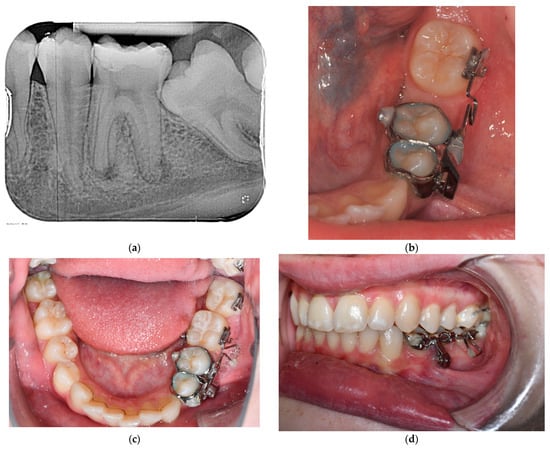

3.3. Treatment Progress

3.4. Treatment Results